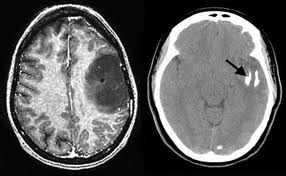

Tumor detection

MRI CT-SCAN

Note: